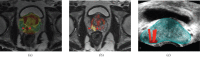

Transrectal ultrasound (TRUS) was first developed in the 1970s. TRUS-guided biopsy, under local anaesthetic and prophylactic antibiotics, is now the most widely accepted method to diagnose prostate cancer. However, the sensitivity and specificity of greyscale TRUS in the detection of prostate cancer is low. Prostate cancer most commonly appears as a hypoechoic focal lesion in the peripheral zone on TRUS but the appearances are variable with considerable overlap with benign lesions. Because of the low accuracy of greyscale TRUS, TRUS-guided biopsies have become established in the acquisition of systematic biopsies from standard locations. The number of systematic biopsies has increased over the years, with 10-12 cores currently accepted as the minimum standard. This article describes the technique of TRUS and biopsy and its complications. Novel modalities including contrast-enhanced modes and elastography as well as fusion techniques for increasing the sensitivity of TRUS-guided prostate-targeted biopsies are discussed along with their role in the diagnosis and management of prostate cancer.